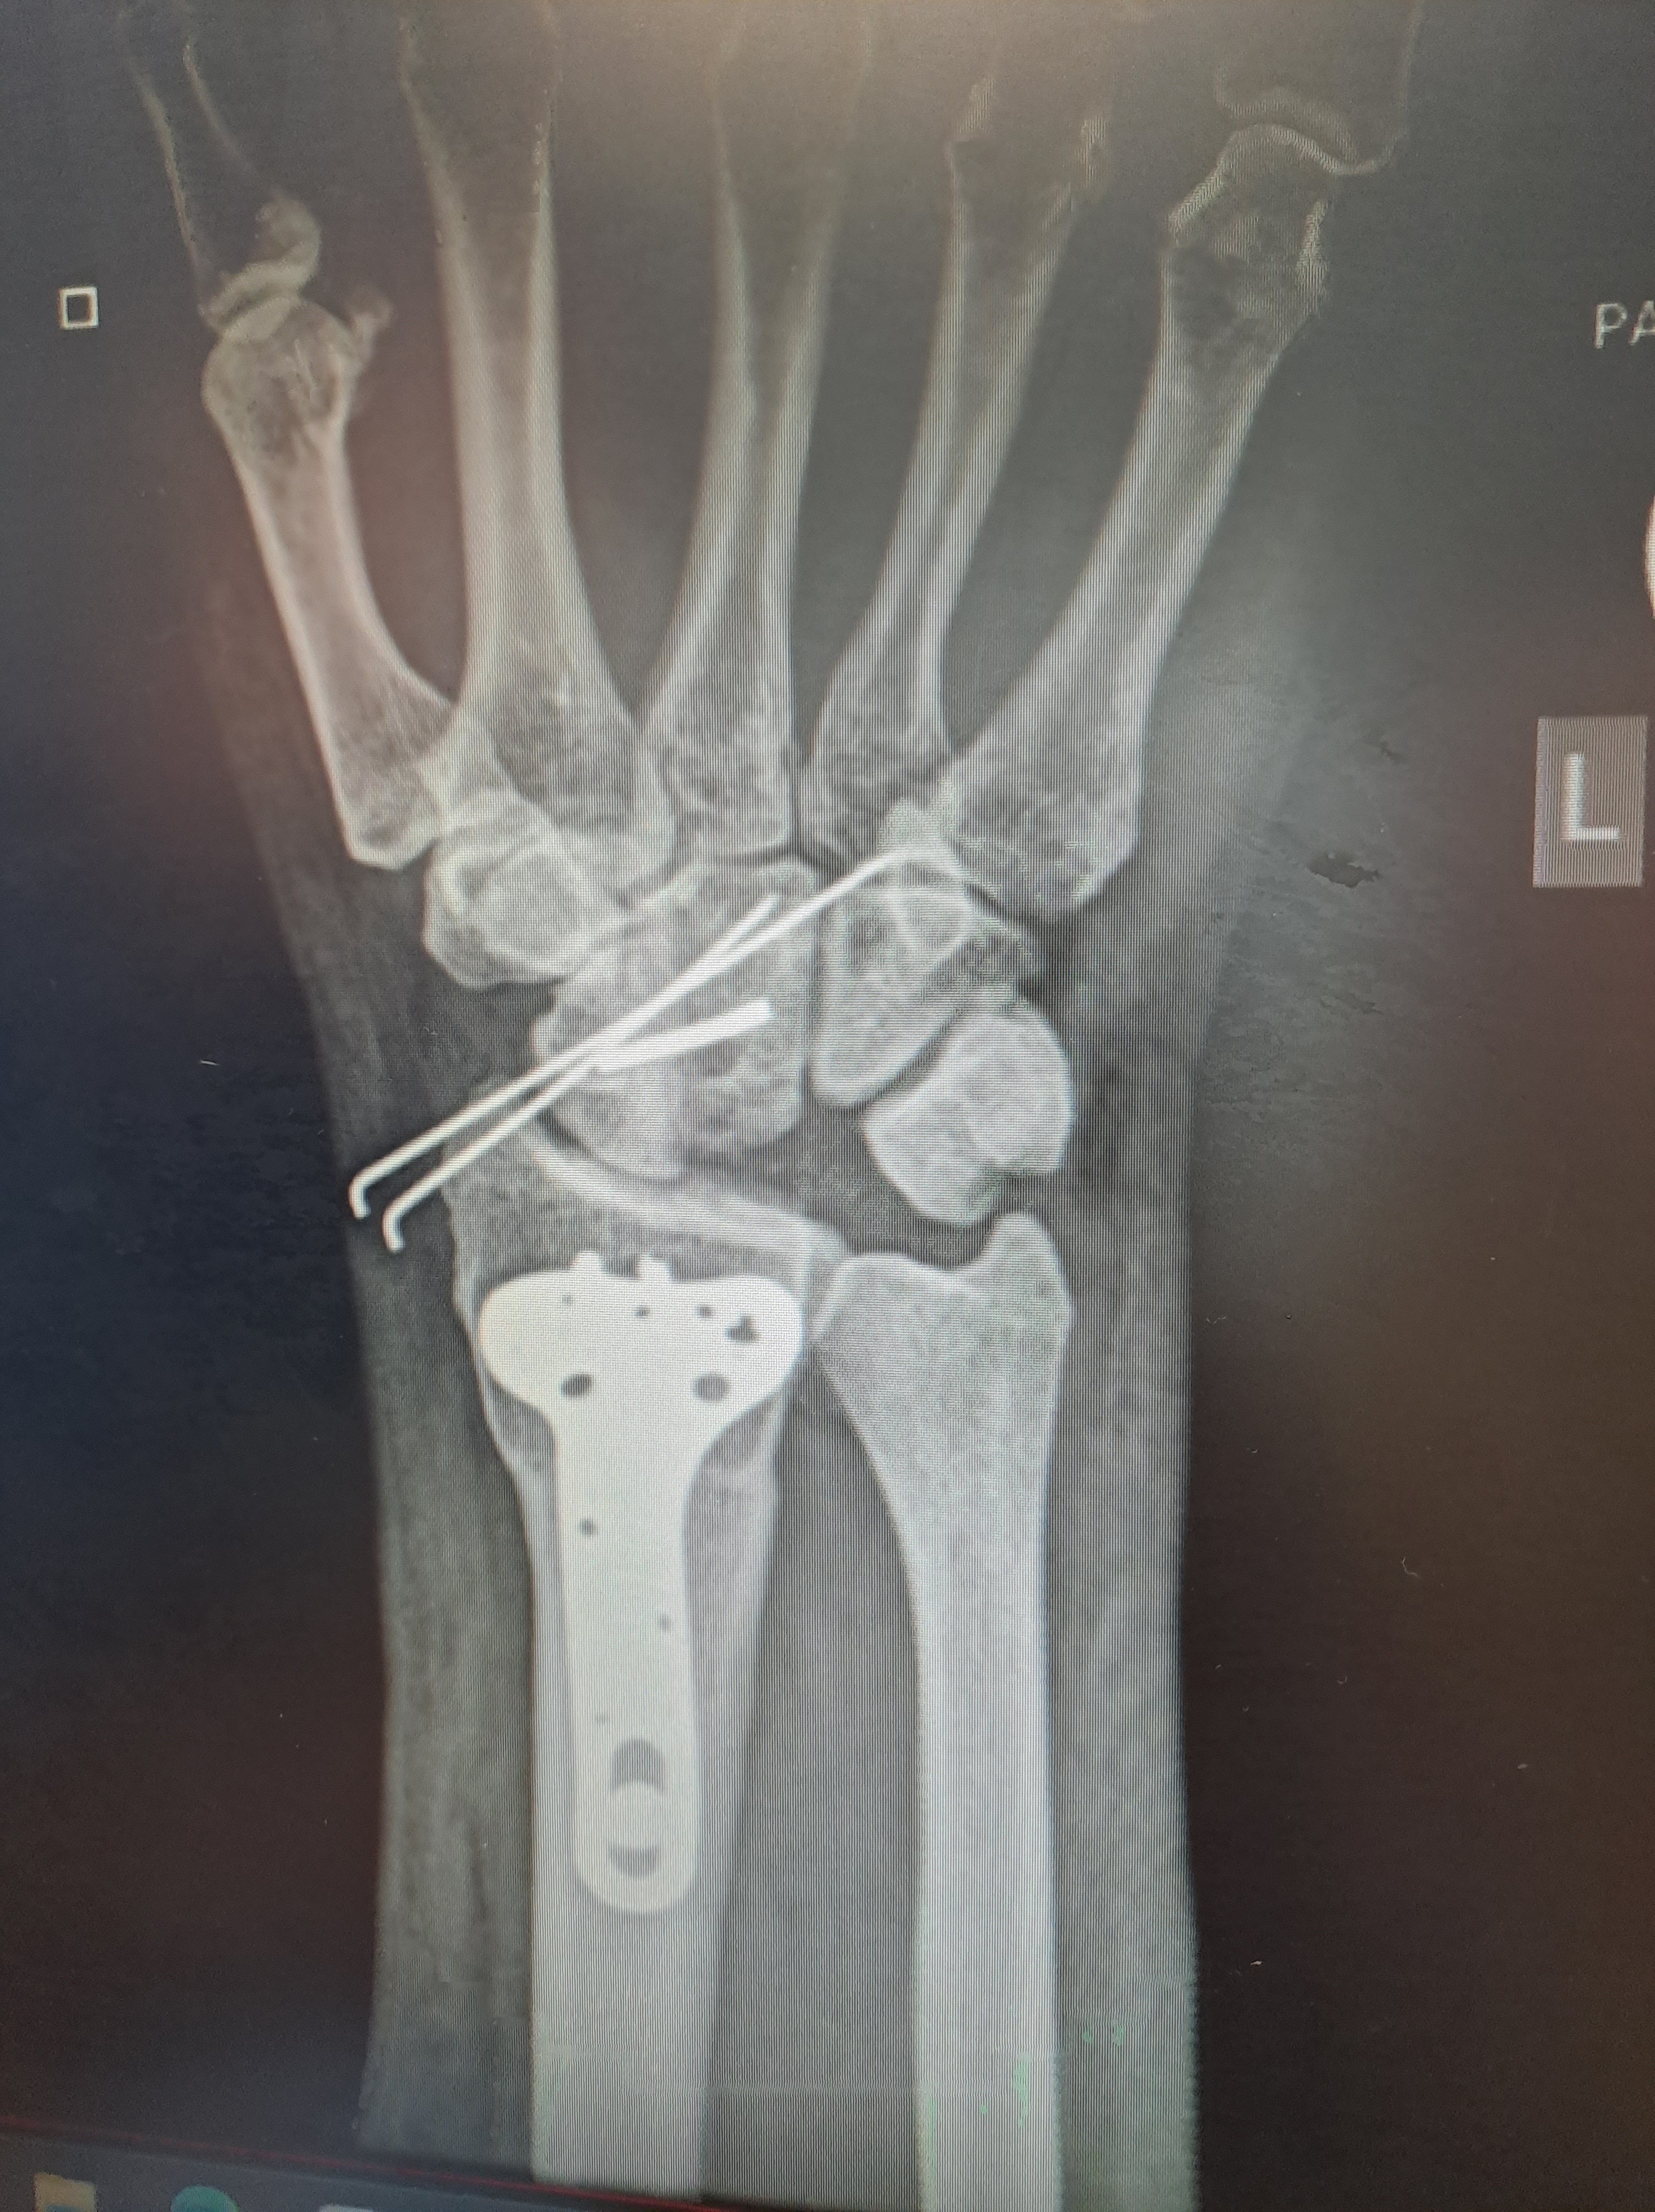

Image 2: An x-ray of a hand with a lunate that has died, the shadowed bone.